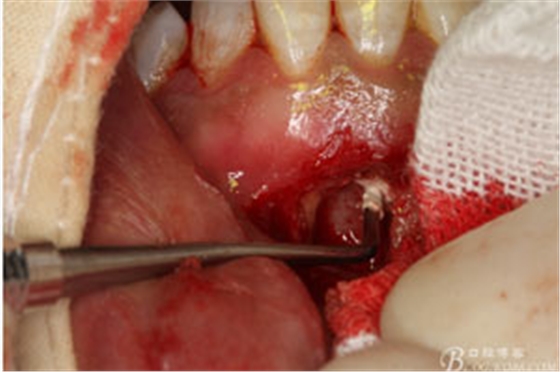

圖8.超聲骨刀去除根尖周圍感染骨質(zhì)

圖9.清晰可見牙膠從31根尖1/3溢出。